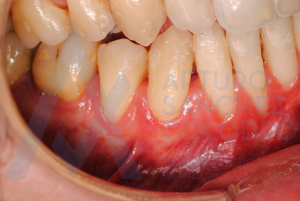

Estas son las imágenes obtenidas de exploración intraoral inicial: